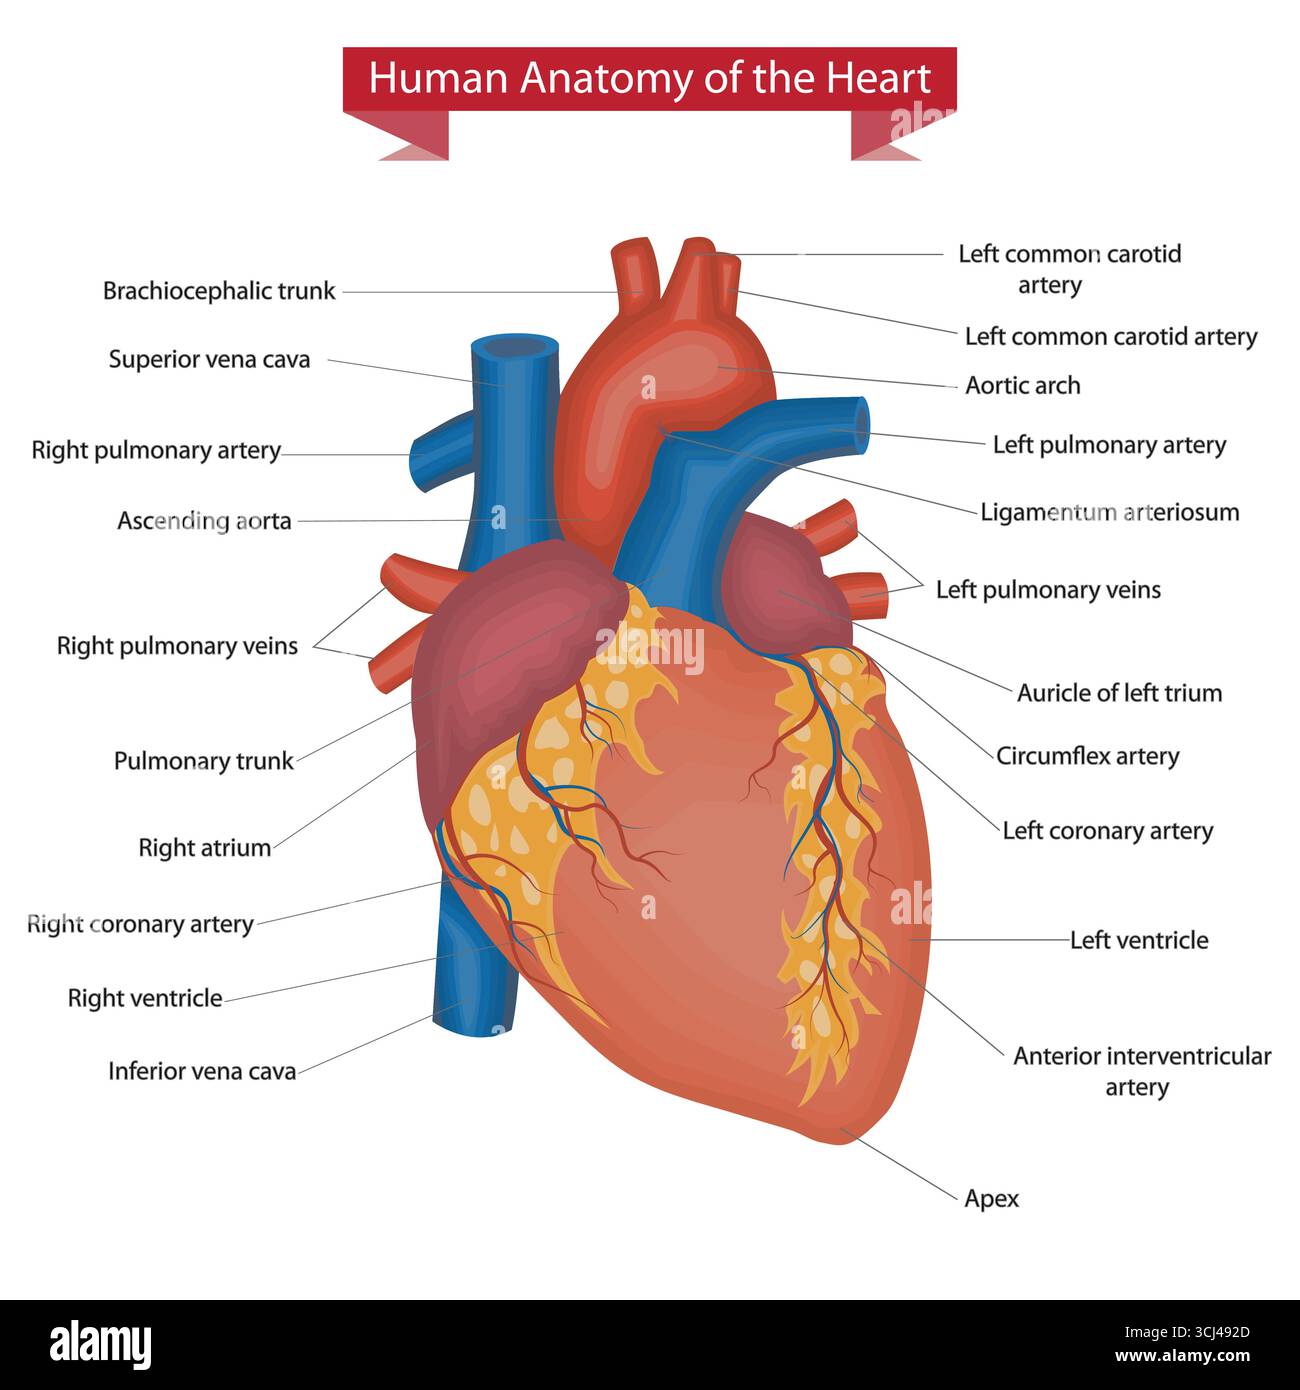

Detailed anatomical illustration of the human heart with labelled parts and major vessels. Stock Vectorhttps://www.alamy.com/image-license-details/?v=1https://www.alamy.com/detailed-anatomical-illustration-of-the-human-heart-with-labelled-parts-and-major-vessels-image699573461.html

Detailed anatomical illustration of the human heart with labelled parts and major vessels. Stock Vectorhttps://www.alamy.com/image-license-details/?v=1https://www.alamy.com/detailed-anatomical-illustration-of-the-human-heart-with-labelled-parts-and-major-vessels-image699573461.htmlRF3CJ492D–Detailed anatomical illustration of the human heart with labelled parts and major vessels.